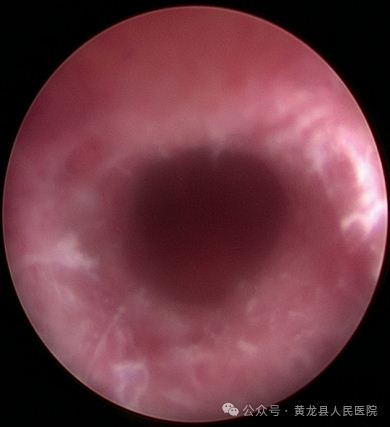

经宫腔镜宫腔粘连分离术+宫腔镜子宫内膜息肉切除术。

患者赵某,58岁,绝经后B超提示子宫内膜增厚8天。患者合并高血压,高血脂、盆腔炎,入院后给予降压、调脂、抗感染治疗后行宫腔镜检查术,术中见宫腔中上部可见一纤维状粘连,宫底及双侧输卵管开口不可见,宫腔下段前后壁分别可见一枚赘生物,大小约1×0.2cm、0.5×0.2cm,实施宫腔镜宫腔粘连分离术及宫腔镜子宫内膜息肉切除术,术后病检:子宫内膜息肉。

术前宫腔术后宫腔